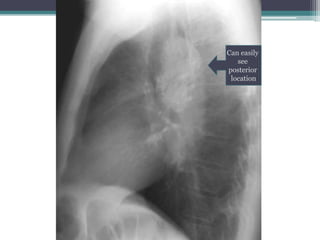

โ€ข Answer: Mass is in posterior mediastinum. We

know because it remains sharply outlined in apex of

thorax, indicating that it is surrounded by lung.

โ€ข This particular example is a ganglioneuroma